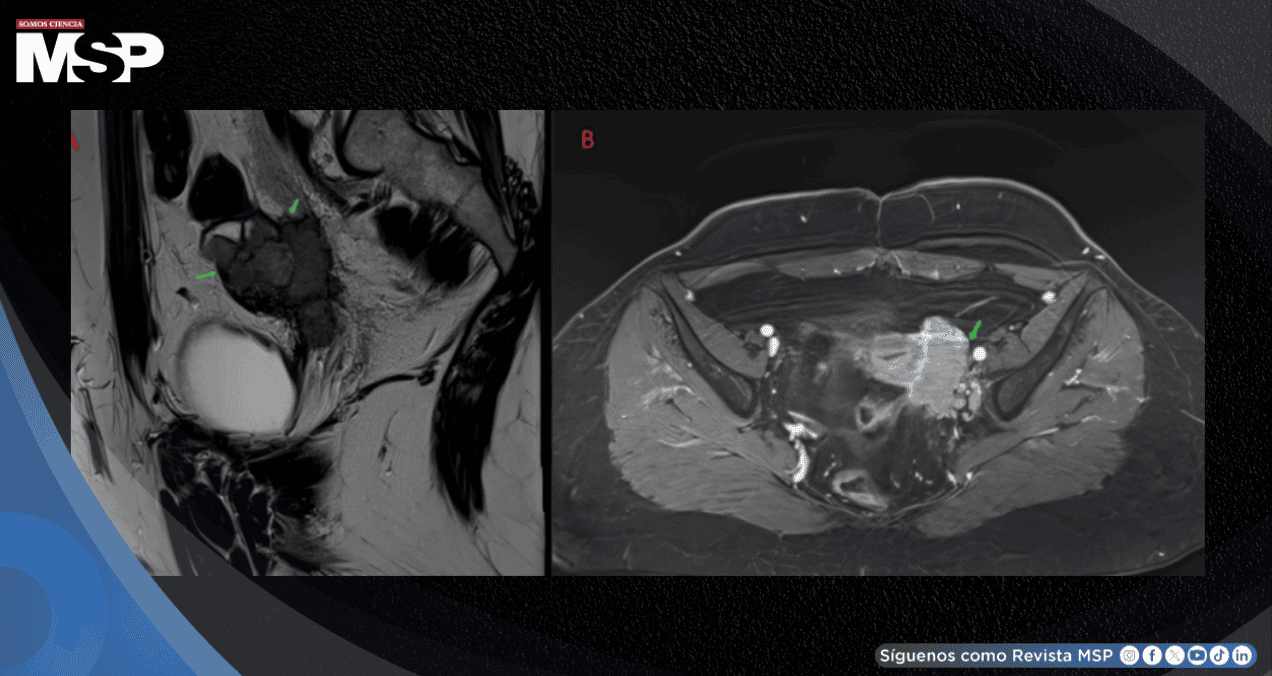

Para obtener una caracterización más precisa, se realizó una resonancia magnética pélvica que confirmó la presencia de una masa sólido-quística originada en el ovario izquierdo, con dimensiones de 65 por 50 milímetros.

El componente quístico mostró un comportamiento típico en las imágenes, mientras que el componente sólido presentó realce tras la administración de contraste, un hallazgo que sugiere actividad tumoral. Adicionalmente, se realizó una tomografía computarizada de tórax, abdomen y pelvis que descartó la presencia de lesiones secundarias o metástasis a distancia.

La apariencia ecográfica del estruma ovárico es inespecífica y puede asemejarse a cualquier masa maligna sospechosa con características sólidas y quísticas mixtas. Sin embargo, la resonancia magnética pélvica permite una mejor caracterización.

El estruma ovárico a menudo se presenta como un tumor multilobulado con áreas quísticas heterogéneas. Los quistes con contenido hemorrágico muestran señales características, mientras que los quistes con contenido coloide muestran baja señal en las diferentes secuencias.

El componente sólido generalmente aparece como una masa que se realza tras la inyección de contraste, tal como se observó en esta paciente.